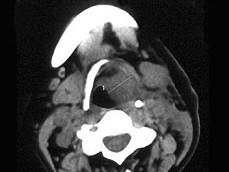

女,54岁,鼻咽部异物感约3个月,PE:左侧声带固定,可见肿物,CT如图所示,应诊断为 ( )

鼻咽癌( )